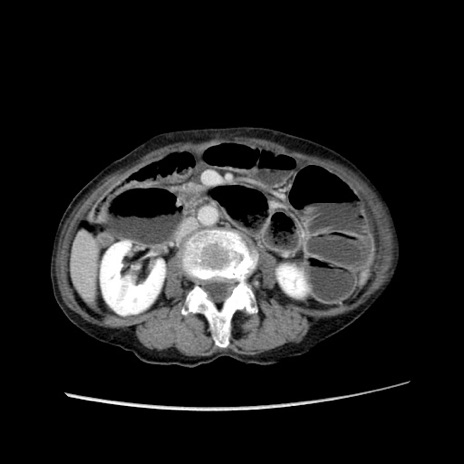

症例25(横断像)

【症例】80歳代女性

【主訴】胸のつかえ感

【現病歴】約9時間前に食後から胸のつかえた感じあり、嘔吐あり、来院。

【既往歴】胃癌(全摘)、胆摘、虫垂炎

【身体所見】心窩部に圧痛あり、反跳痛なし。

【データ】WBC 5700、CRP 0.05